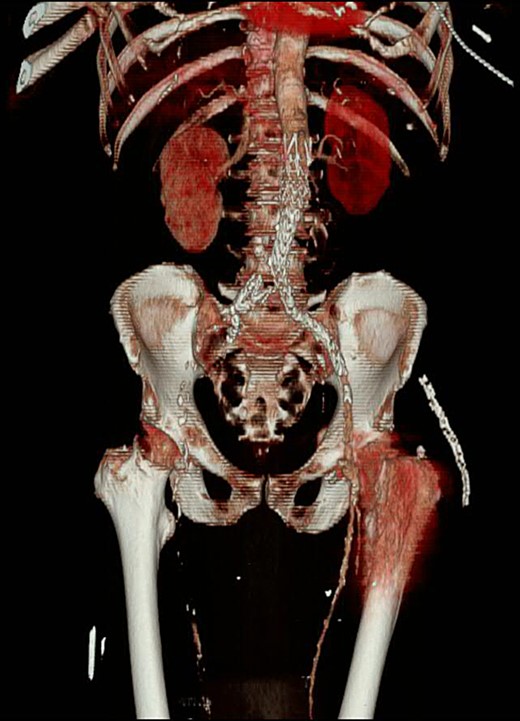

Immediately following the THR in the recovery area, it was then noted that the right lower limb skin was mottled and cool to touch with the complete absence of pulses. The left lower limb was perfused normally. Urgent vascular opinion was sought and a computed tomography (CT) angiogram was performed. This showed a complete filling defect of all vessels down to the foot from the level of the femoro-femoral crossover graft (Fig. 5).

CT angiogram with three-dimensional reconstruction revealing a filling defect to the right lower limb with an absence of collateral circulation.